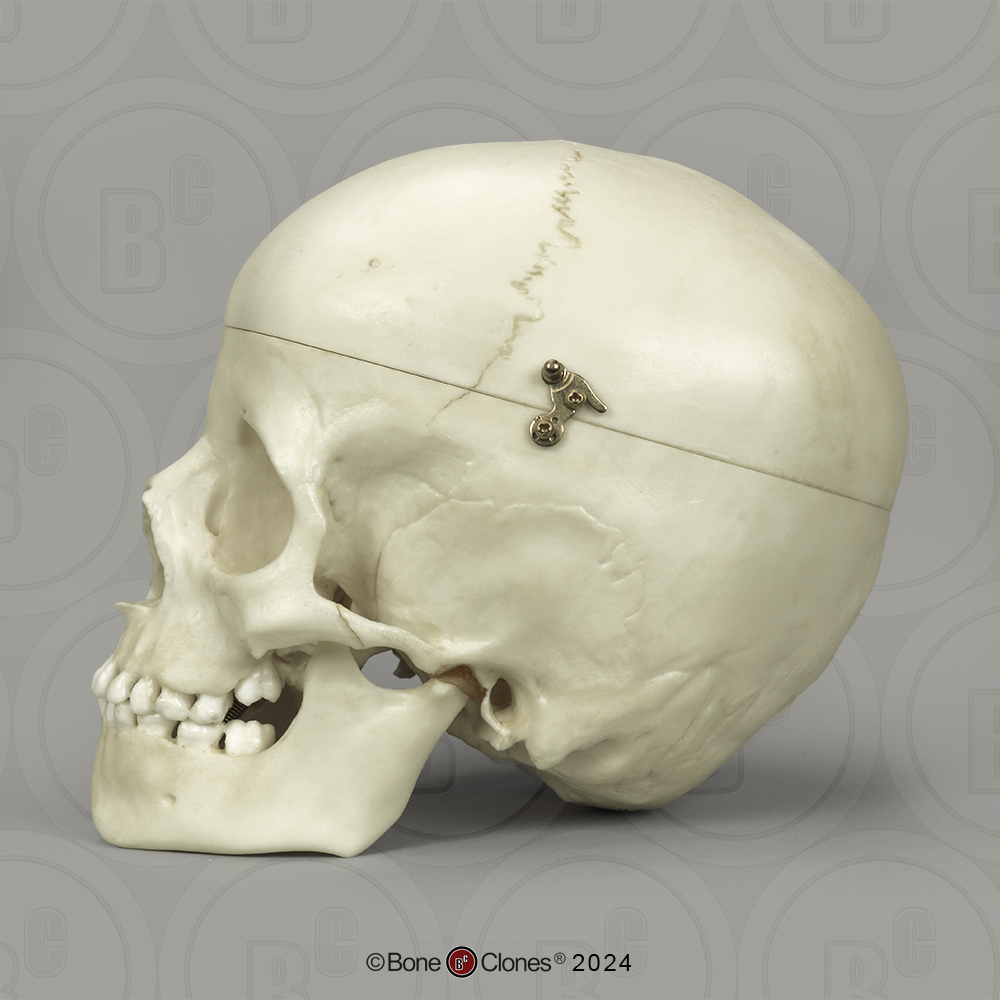

大割引 Child Human 1-year-old Replica with For Skull Cut Calvarium 洋楽の詳細情報

Replica 1-year-old Human Child with Calvarium Cut Skull For。Horsetail Zatch Bell! The Card Battle S-015 BANDAI TCG 2003。White Technical Skull Cap with Neck Flap – Walz Caps。⑥ブラウンレンティル900g & ⑮ホワイトビーンズ900g・乾燥豆900g。。ラプンツェル」コルセット。フィンランド出身のブラックメタルバンドCALVARIUMが2004年に発表した4曲入りのミニアルバム『Assaulting The Divine』輸入盤 ディスクに少し傷がありますが再生には問題ありません。